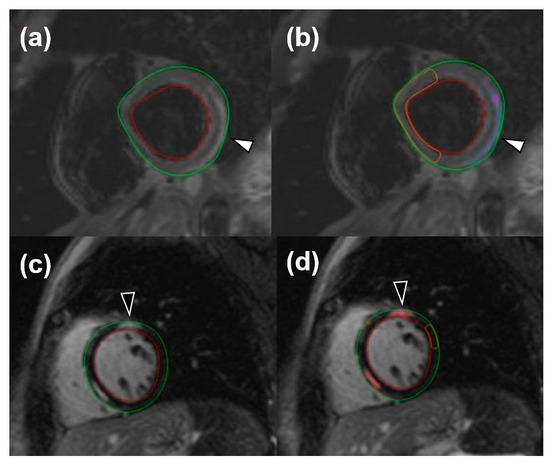

For image analysis, the QMass post-processing tool (Medis Suite MR Software, Medis Medical Imaging Systems, Leiden, The Netherlands) was used. Cine sequences were manually bordered to obtain left ventricle functional data such as end-diastolic volume index, end-systolic volume index, stroke volume, and ejection fraction. Short-axis turbo inversion recovery magnitude sequences were also manually bordered; a threshold of 2 standard deviations (SD) was used to identify edema. Short-axis LGE sequences were manually bordered, and a 6-SD threshold was used to identify enhanced areas. Image analysis for edema was performed twice by one reader and once by a different reader. An example of automatic LGE and edema quantification can be viewed in Figure 1.

Figure 1. Short-tau inversion recovery images for the visualization of edema (white arrowheads) both without (a) and with (b) an automatic quantification mask of remote myocardium and late gadolinium enhancement (black arrowheads), without (c) and with (d) an automatic quantification mask of remote myocardium.